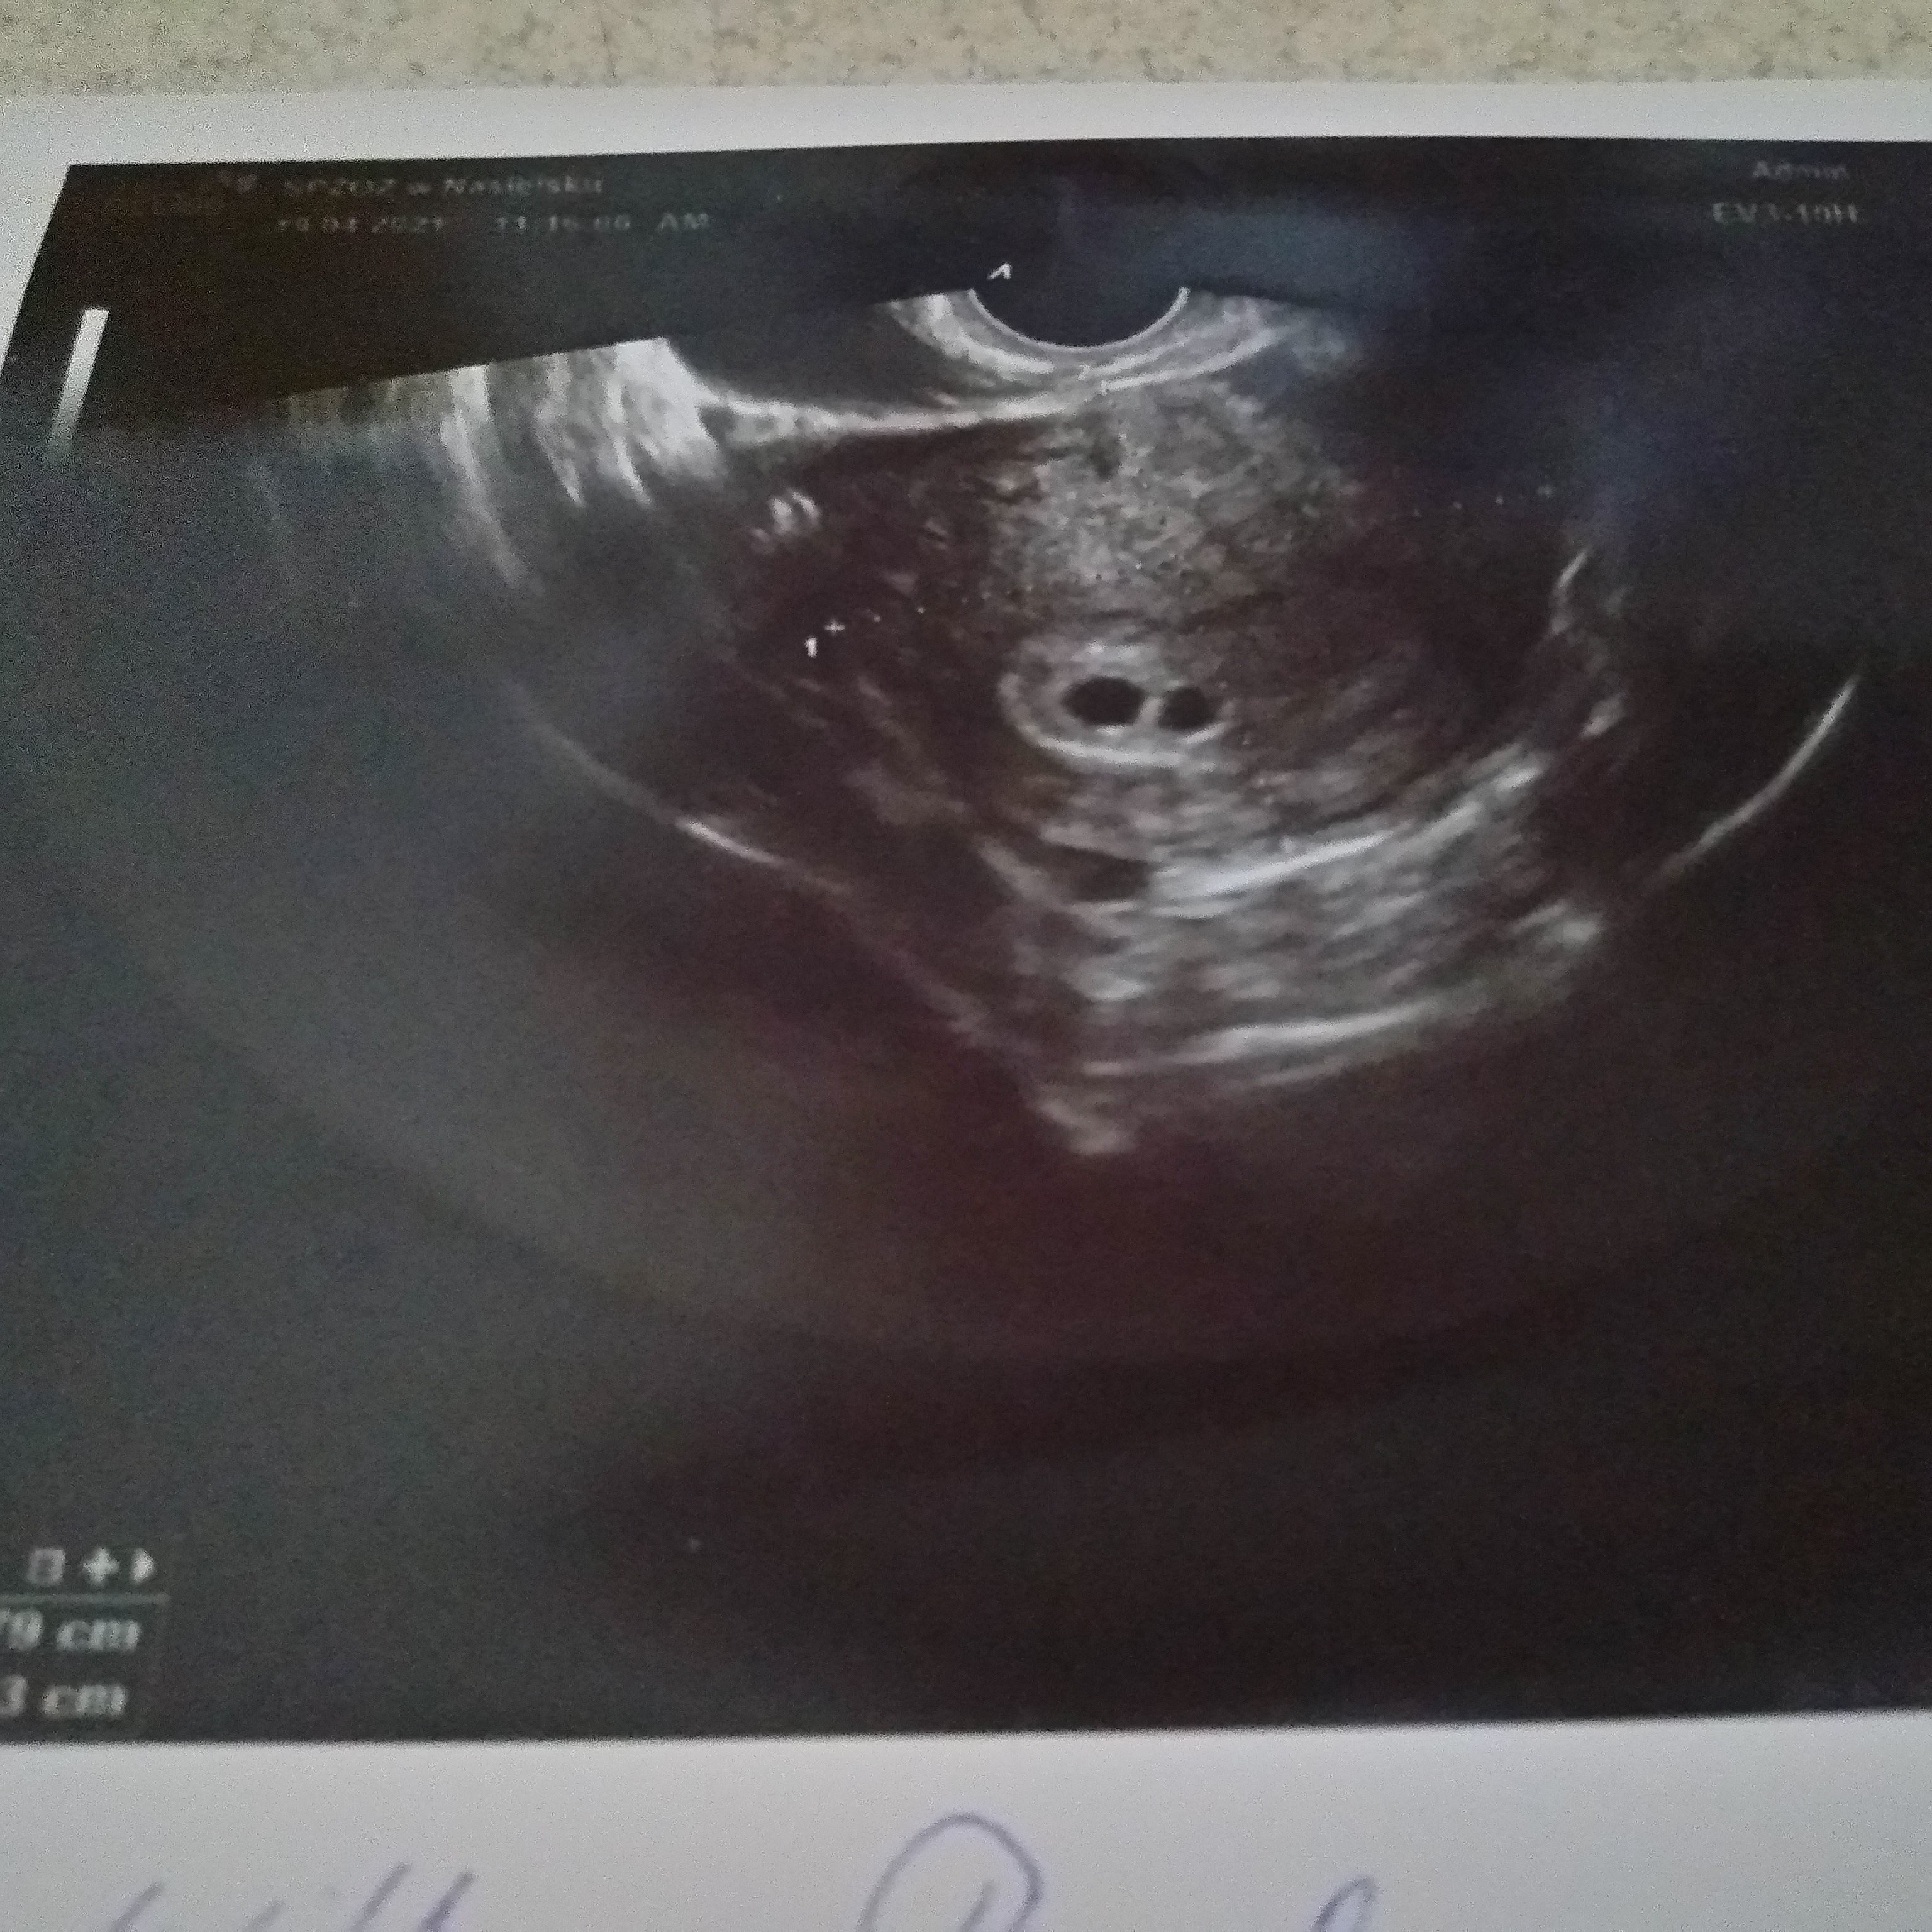

Jestem po ciąży pozamacicznej, która miała miejsce w lutym, 5 marca miałam ostatnią miesiączkę, 19 kwietnia ( licząc od OM był to 6 tydzień i 4 dzień) byłam u ginekologa który potwierdził ciążę w macicy, 2 pęcherzyki ciążowe, niestety nie dostrzegłam zarodków ani pęcherzyków żółtkowych, mój ginekolog nie mówi za dużo i nie udzielił mi nawet informacji który wg niego to tydzień, kiedy przewiduję termin porodu, dostałam tylko skierowanie na badania) bardzo mnie to zmartwiło, to moja pierwsza ciąża ( właściwie umiejscowiona), może któraś z Pań widzi coś na tym USG? Albo jest jeszcze za wcześnie by zobaczyć zarodek? Bardzo się martwię... Z góry dziękuję za odpowiedzi!

Na wydruku masz podane wymiary 0.6cm i 0.5 to wychodzi mniej więcej 5 tydzień